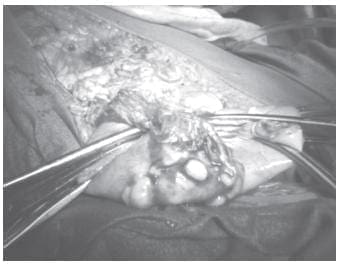

Con estos hallazgos, se decidió someterla a laparotomía exploradora inmediata. En la intervención se descubrió una moderada cantidad de ascitis no hemorrágica, un útero muy pequeño, tumoración de ambos ovarios, la del izquierdo de 15 cm de diámetro y la del derecho de 8 cm, ambas de aspecto cerebroide; en el íleon terminal se encontró una masa de 9 cm con varios ganglios linfáticos, así como ganglios en la cola del páncreas, y tumoración de 8 cm de diámetro, aproximadamente, de la glándula suprarrenal izquierda. Se realizó salpingoooforectomía bilateral, suprarrenalectomía izquierda con resección de los ganglios de la región distal pancreática y resección segmentaria del íleon y meso, que incluyó varios ganglios, con anastomosis término-terminal (figuras 7 y 8).

FIGURA 7. Tumor de ovario.

FIGURA 8. Tumor en el íleon terminal.